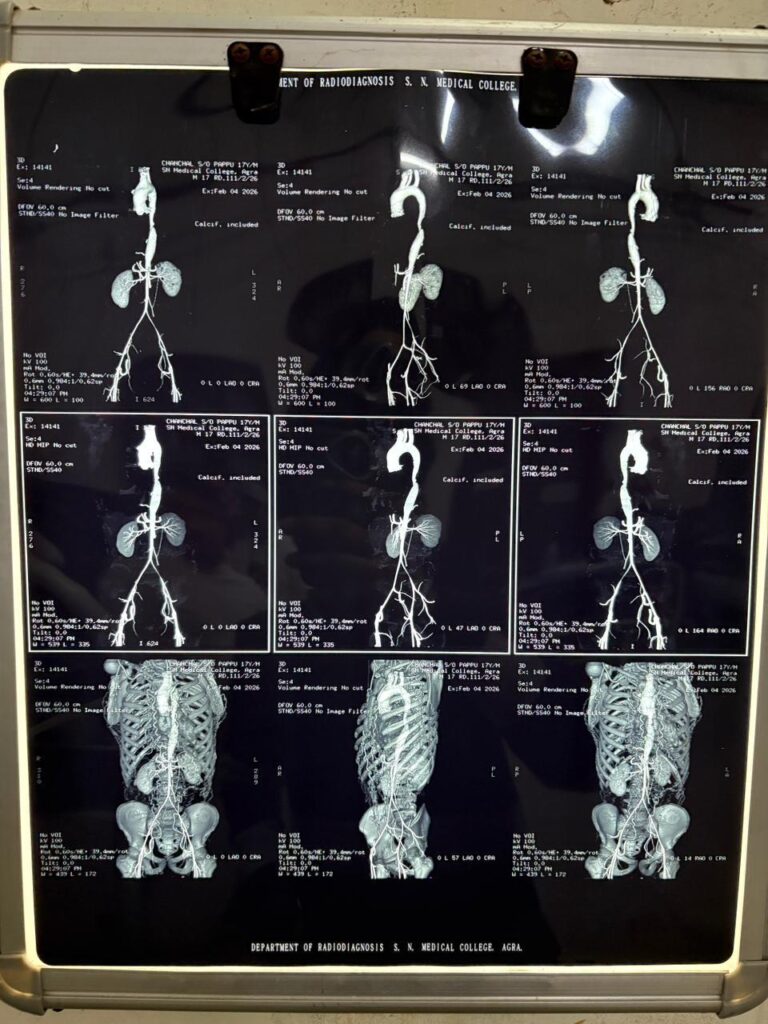

बाल के बराबर पतली रह गई थी मुख्य धमनी: ऐसे हुआ डायग्नोसिस मरीज को गंभीर हालत में एस.एन. मेडिकल कॉलेज के मेडिसिन विभाग में भर्ती कराया गया। यहां मेडिसिन विभाग के विशेषज्ञ डॉ. शिवांग शर्मा और डॉ. हरि सिंह ने मरीज की गहनता से जांच शुरू की। तमाम आधुनिक पैथोलॉजी और रेडियोलॉजी जांचों के बाद जो सच सामने आया, उसने डॉक्टरों को भी चौंका दिया।

मरीज ‘कोआर्कटेशन ऑफ एओर्टा’ नामक जन्मजात हृदय रोग से ग्रसित पाया गया। इस बीमारी में दिल से पूरे शरीर में शुद्ध खून ले जाने वाली सबसे बड़ी और मुख्य धमनी (Aorta) सिकुड़ जाती है। इस 17 वर्षीय किशोर के मामले में यह सिकुड़न इतनी ज्यादा थी कि मुख्य धमनी में लगभग 99% तक रुकावट आ चुकी थी और वह सिकुड़कर सिर्फ एक इंसानी ‘बाल’ के बराबर पतली रह गई थी। इसी रुकावट के कारण खून शरीर के निचले हिस्से (पैरों) तक नहीं पहुंच पा रहा था और सारा दबाव वापस लौटकर दिमाग और शरीर के ऊपरी हिस्से पर पड़ रहा था, जिसने उसे ब्रेन हैमरेज का शिकार बना दिया था।

दो सप्ताह की प्लानिंग और डॉ. हिमांशु यादव का ऐतिहासिक ऑपरेशन बीमारी का सटीक पता चलने के बाद मामला कार्डियोलॉजी विभाग को सौंपा गया। एस.एन. मेडिकल कॉलेज के जाने-माने कार्डियोलॉजिस्ट डॉ. हिमांशु यादव ने इस चुनौती को स्वीकार किया। यह कोई सामान्य एंजियोप्लास्टी नहीं थी। मुख्य धमनी (एओर्टा) में स्टेंट डालना एक अत्यंत जटिल और जोखिम भरा काम होता है, जिसमें जरा सी चूक मरीज की जान ले सकती है।

डॉ. हिमांशु यादव और उनकी टीम ने इस ऑपरेशन के लिए लगातार दो सप्ताह तक विस्तृत योजना (Homework and Planning) बनाई। इसके बाद, बिना किसी बाहरी विशेषज्ञ (Outside Expert) की मदद के, डॉ. यादव ने स्वयं इस जटिल स्टेंटिंग प्रक्रिया को सफलतापूर्वक अंजाम दिया। अत्याधुनिक कैथ लैब (Cath Lab) में किए गए इस ऑपरेशन के दौरान सिकुड़ी हुई धमनी को गुब्बारे (Ballooning) की मदद से फुलाया गया और फिर वहां एक विशेष स्टेंट (Stent) लगा दिया गया ताकि वह दोबारा न सिकुड़े।